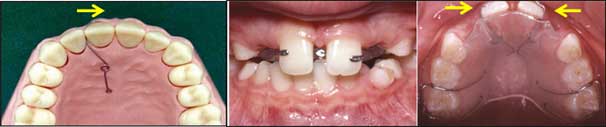

أ - أجزاء الجهاز التقويمي الثابت:

1. الأطواق bands: هي شرائط معدنية تحيط بالسن يلحم عليها وصلات دهليزية ولسانية، ويمكن استخدام المقامط (التيوبات) الملصقة دهليزياً على الأرحاء في حال عدم الحاجة للوصلات اللسانية (الشكلان 13 و14).

2. الحاصرات brackets: تتألف من أجنحة wings يطبق عليها مطاط أو أسلاك الربط، مع شق أفقي slot لإدخال سلك التقويم، وتقسم بحسب ارتفاع الشق إلى نظامين 0.46 مم و0.56 مم، ويتفاوت عمق الشق بين 0.64 مم و0.82 مم. تطبق الحاصرات إلى السطوح السنية بالاعتماد على الإدخال الميكانيكي للمادة اللاصقة ضمن فراغات الشبكة الموجودة في قاعدة الحاصرة. وقد طورت حاصرات خزفية بهدف تحسين المظهر الجمالي (الشكل 15).

مراحل إلصاق الحاصرات التقويمية:

- الإلصاق المباشر: تُلصق مباشرة سريرياً، ويجب تحري التوضع الدقيق للحاصرات في الاتجاهات الثلاثة (الشكل 16).

- الإلصاق غير المباشر: يتميز بإنقاص الزمن السريري مقارنة بالإلصاق المباشر (الشكل 17).